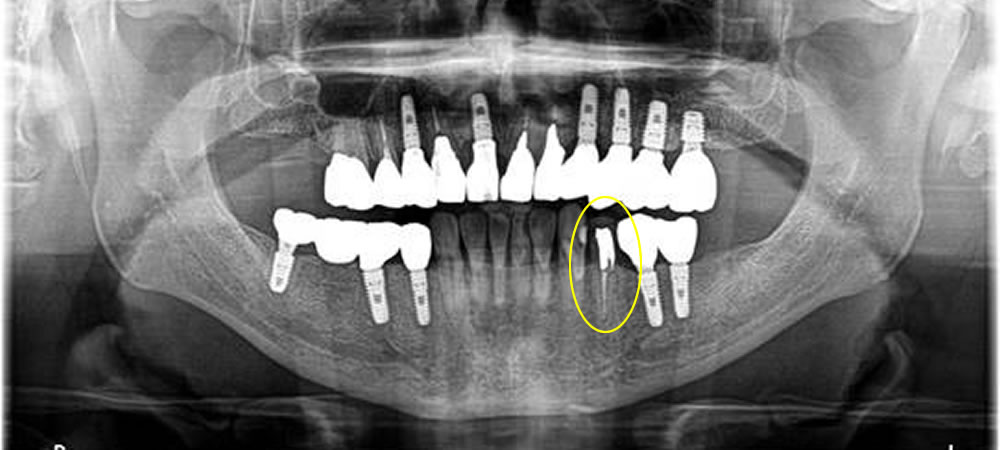

レントゲン検査等したところ、神経を取った歯の治療後予後が悪く根っこが破折していることが判明しました。患者さまと相談し、破折歯を抜歯後にインプラント治療にて咬み合わせを回復することになりました。